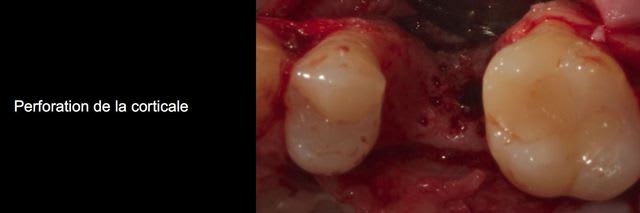

Bon ben voilà j'ai réalisé une ROG avec une membrane PTFE armé titane.

bien sûr les photos sont dans le désordre encore une fois ;)